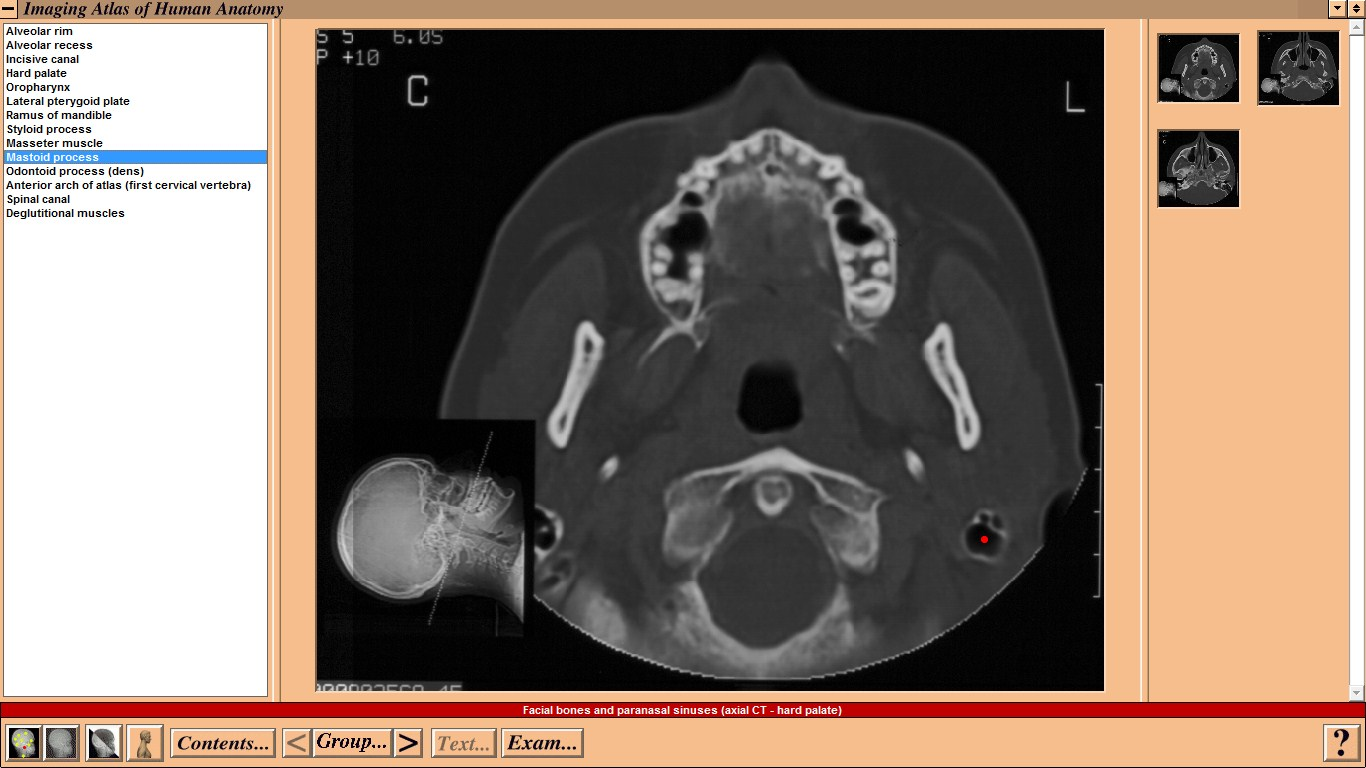

Mosby - Imaging Atlas of Human Anatomy by Jamie Weir and Peter H. Abrahams - CD-ROM Год выпуска: 1995 Версия: 1.0 Разработчик: Mosby Платформа: WindowsСовместимость с Vista: неизвестно Системные требования: IBM or compatible PC, 486SX, 8MB RAM, 640 × 480 display, 256 colors, double speed CD-ROM drive, Microsoft Windows 3.1 or later, optimum: Pentium processor, 800 × 600 display, more than 256 colors, ISBN 0-7234-2187-0, St Louis, Mo, Mosby, 1995 Язык интерфейса: только английский Таблэтка: Не требуется Описание: This CD-ROM provides a detailed atlas of radiologic anatomy in all forms, including plain films, magnetic resonance (MR) imaging, computed tomography (CT), venography, and angiography. It is formatted to present a concise atlas, cephalad (skull) to caudad (feet). The disc is easy to work with, and I did not have any trouble setting it up. The graphics and table of contents are laid out well. Navigating the various parts is relatively simple. The opening graphics are well displayed, allowing instant access to pictures or the table of contents; therein lies the simplicity of finding an anatomical part of the body to review. Each screen contains a picture of the radiograph accessed, key landmarks (with a glossary that can be turned off), related slides that can easily be accessed, and a self-exam. Диск содержит более чем 3500 радиографических изображений нормальной анатомии, включая обычные рентгенограммы, КТ, МРТ, ангиограммы, артериограммы и видео УЗИ. Исчерпывающий уровень анатомических ориентиров с возможностью самоконтроля. Издание рассчитано прежде всего на рентгенологов. Доп. информация: Поскольку издание старое, придется установить древнюю версию Quick Time - 2.0.3.51 (есть на самом диске).   Набор в группу «Хранители» - Помогите сохранить редкие раздачи неделю назад